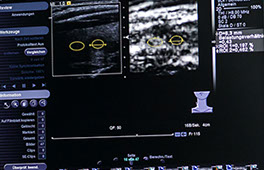

Bei der sonografischen Schilddrüsenuntersuchung werden häufig Knoten gefunden. Da Knoten in seltenen Fällen auch bösartig sein können, aber angesichts der großen Zahl neu entdeckter Knoten nicht alle Befunde zur endgültigen Klärung punktiert oder gar operiert werden können, sind die sonografischen Unterscheidungsmerkmale besonders wichtig.

Mit der Elastografie ist nun ein wertvolles zusätzliches Merkmal, die Festigkeit eines Knotens, hinzugekommen: je härter, fester, unelastischer ein Knoten ist, desto wahrscheinlicher ist es, dass er aus bösartigen Zellen besteht (dies insbesondere dann, wenn die bereits bekannten Merkmale wie Echoarmut, unregelmäßige Begrenzung, ovale Form, Mehrdurchblutung, Kalkeinlagerungen zusätzlich vorhanden sind).